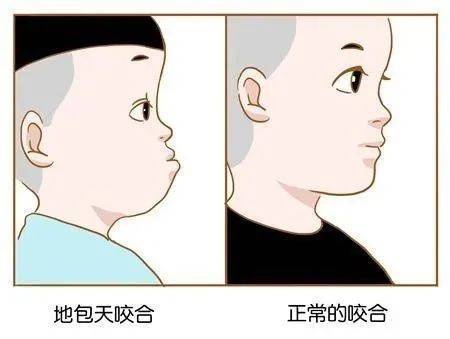

“地包天”的形成因素有很多,最主要的就是遗传因素,但是后天的环境和习惯的影响也不容忽视,主要包括口腔不良习惯和乳恒牙替换期障碍。 “地包天”会影响整个口腔、颜面、颌骨的生长发育,对儿童的身心造成很大影响。

地包天儿童与正常儿童最明显的差别就是前者的面中部平坦或凹陷,下颌前突,主要是由于上颌骨的发育受到了下颌骨的限制引起的。